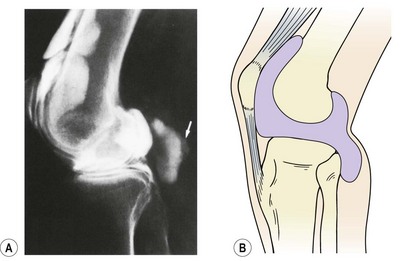

Patellofemoral loads may be as high as three or four times body weight as the knee flexes in walking, and nine times body weight when descending stairs (Cox, 1990). While the posterior surface of the patella is compressed, the anterior aspect receives a tensile force when seen in the sagittal plane (Fig. 9.3B). The effect of the Q angle is to create both horizontal and vertical force vectors which tend to compress the lateral aspect of the patella but submit the medial aspect to tensile stress (Fig. 9.3A). Clearly, alterations in Q angle will change the pattern of stress experienced by the patellar cartilage.

image

Figure 9.3 Patellar stress. (A) The Q angle causes the lateral edge of the patellar cartilage to be compressed, while the medial aspect is subjected to tensile stress. (B) The posterior surface of the patella is compressed. FQ, quadriceps pull; FP, patellar tendon.

From Cox (1990), with permission.